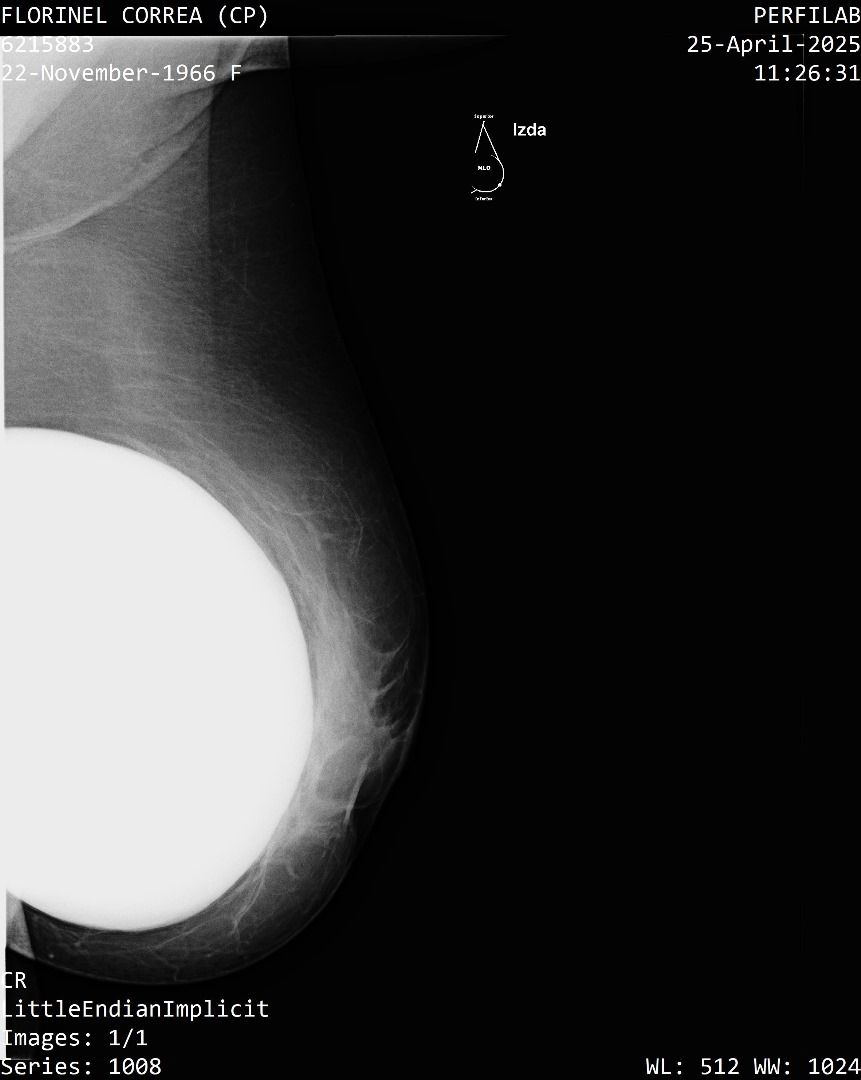

A Correa se le practicó un estudio de mamografía bilateral, la cual reporta una densidad mamaria heterogéneamente densa (ACR C), lo cual puede dificultar la detección de lesiones sospechosas.

Además, la presencia de implantes mamarios limita aún más la visibilidad del tejido mamario.

También se identificó un ganglio linfático de aspecto residual en la axila derecha que se considera sospechoso con este método, requiere evaluación urgente mediante ecografía mamaria.